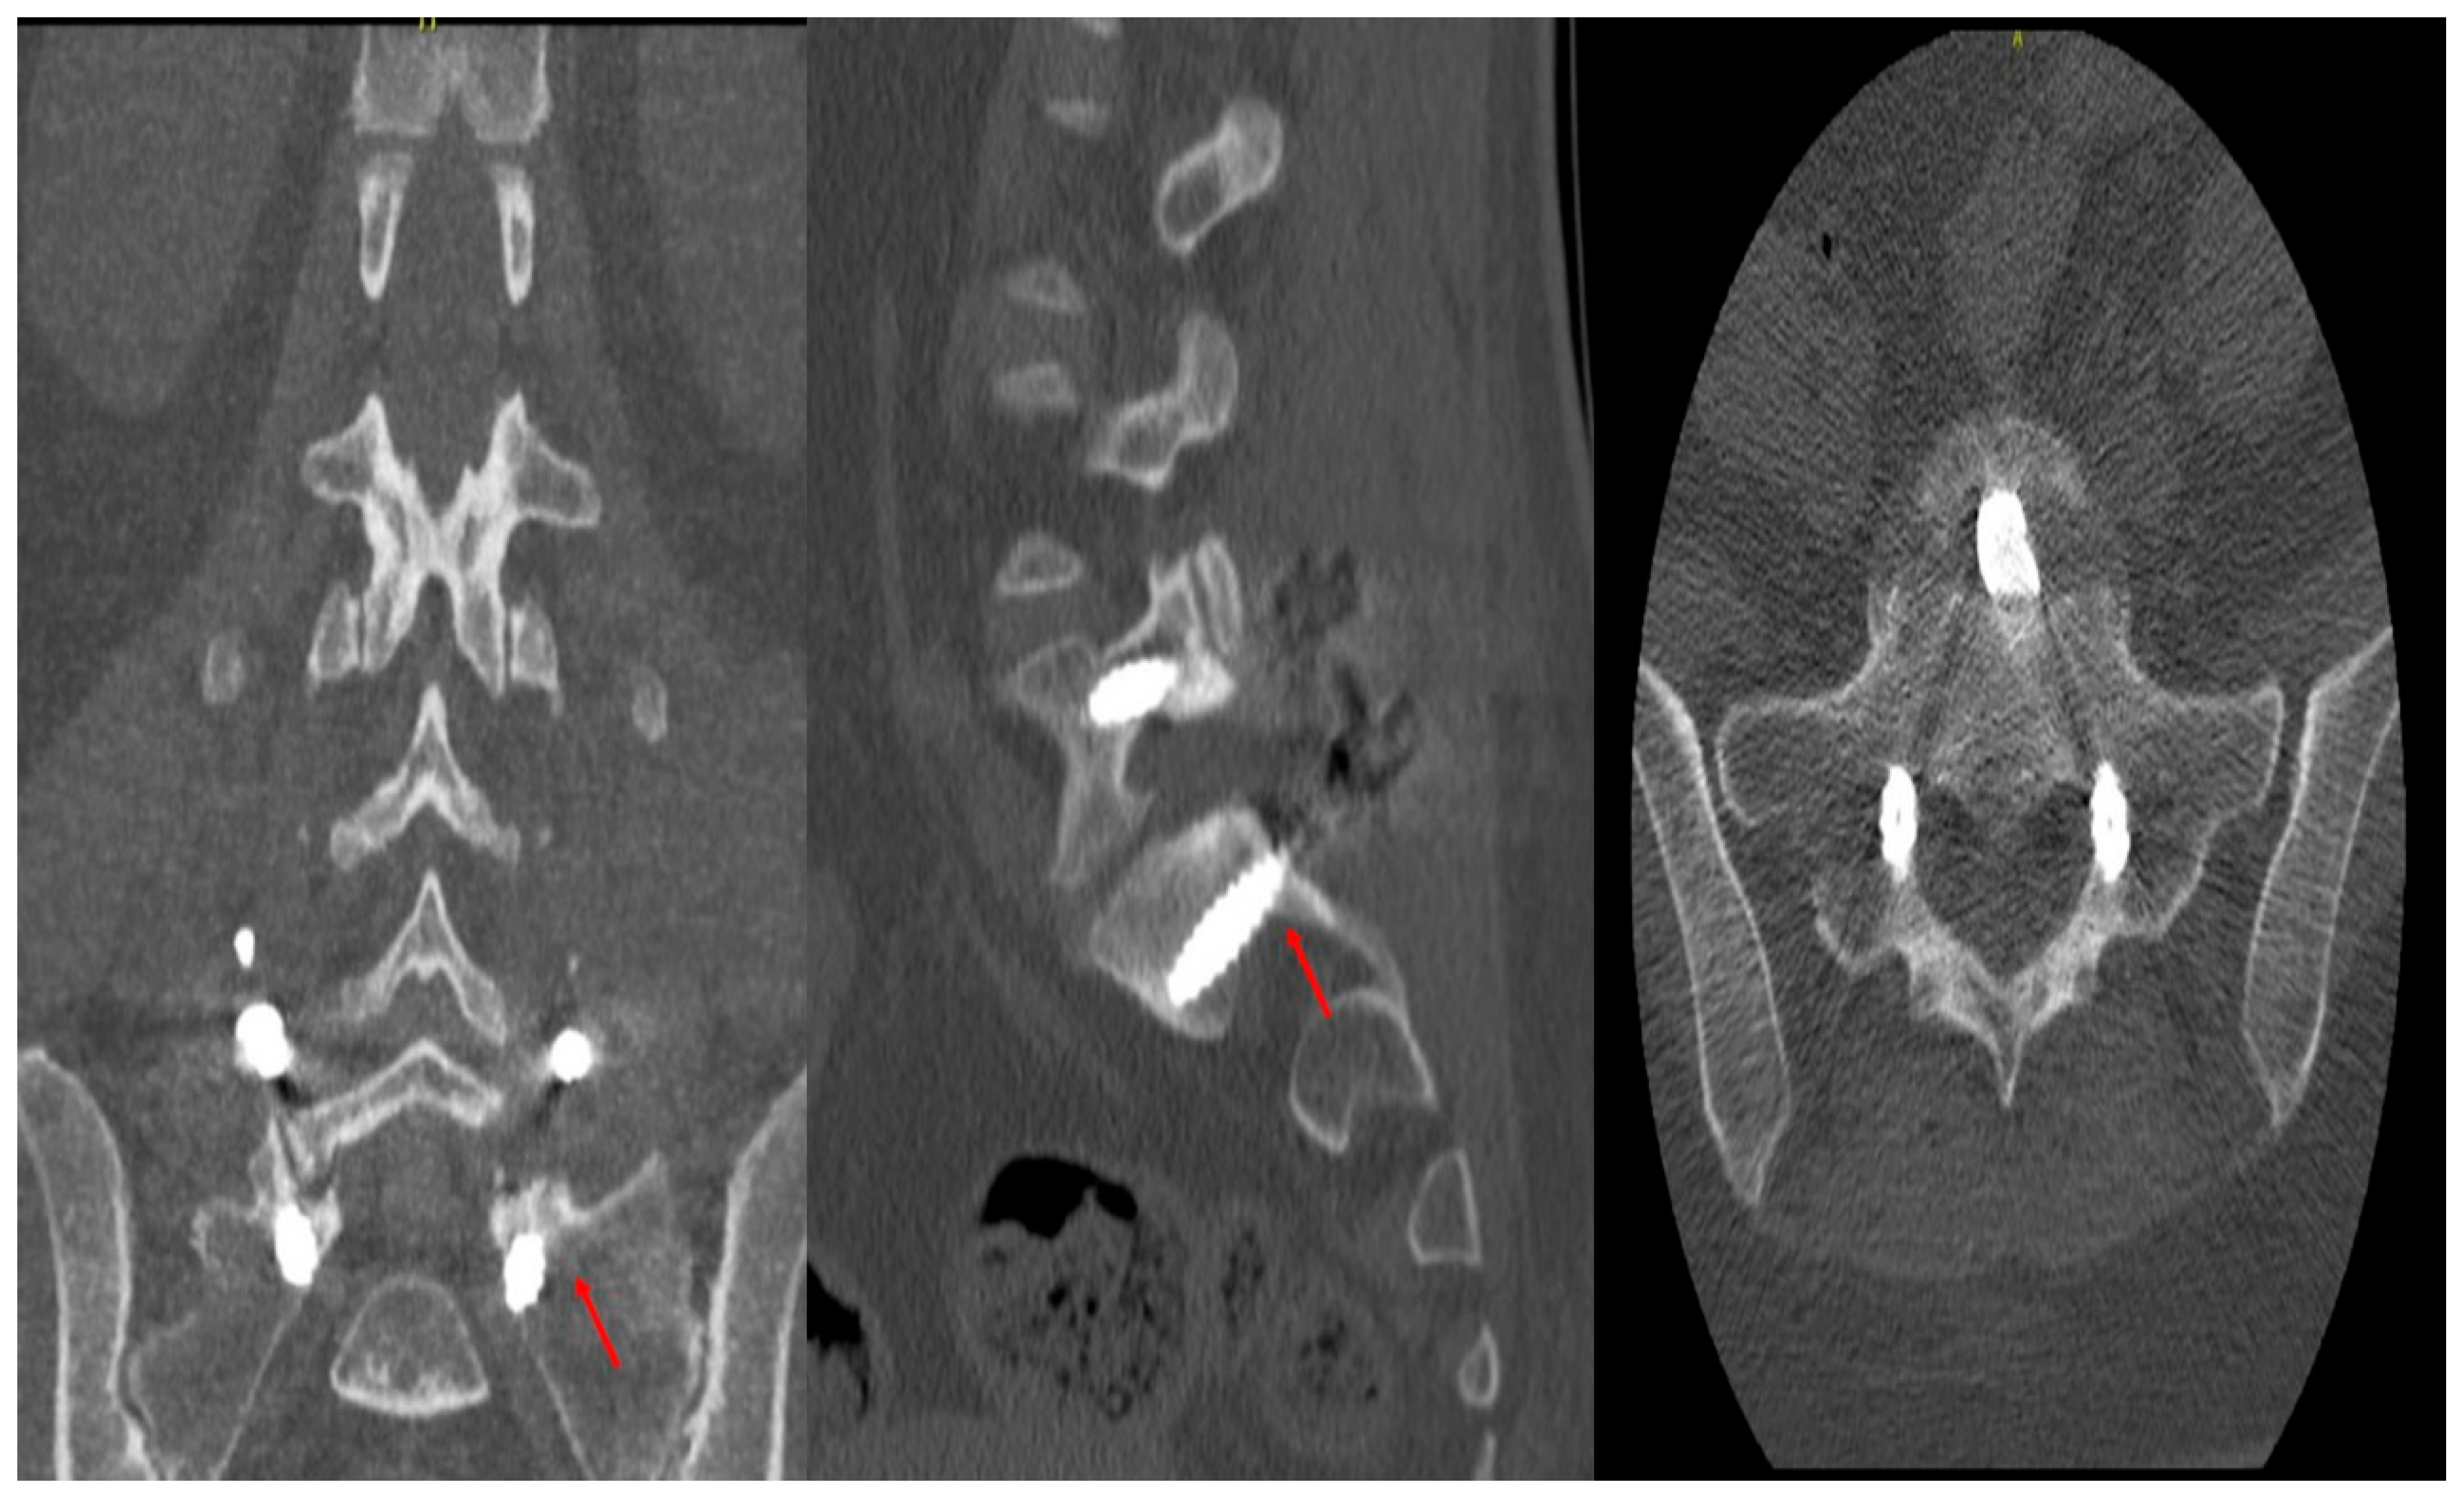

Accuracy of the pedicle screws was assessed using the classification of Gertzbein and Robins (CITA). A four-grade system (A to E) was created to determine the pedicular screws’ position in a postoperative CT scan of the instrumented area (Figure 2). Two fellowship-trained spinal surgeons who did not participate in the surgical procedures and were blind to all patient data and intraoperative results independently assessed postoperative CT scans. Axial and sagittal CT scans were used to assess screw accuracy using the Gertzbein–Robbins classification method. Consensus discussion was used to settle disagreements among reviewers to ensure consistent interpretation across all cases. Fusion was evaluated using postoperative CT scans obtained at approximately 6 months, defined using a bone trabecula passing through the affected area, consistent with our institutional follow-up protocol. We conducted a patient-level analysis, meaning that fusion status was assessed per patient rather than per individual spinal level.

Figure 2. A four-grade system (A to E) was created to determine the pedicular screws’ position in a postoperative CT scan of the instrumented area. In this images, it is possible to see a Grade B medial breach antero-posterior, lateral, and axial views in the CT scan.